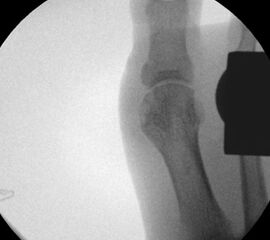

• Röntgenaufnahme des Fußes (unter Belastung) in dorsoplantarem und seitlichen Strahlengang (Abb. 3) und präoperative Fotodokumentation.

• Beurteilung des proximalen Gelenkflächenwinkels der Grundphalanx (Proximal Phalangeal Articular Angle, PPAA) des Hallux valgus interphalangeuswinkels (Hallux interphalangeus Angle, HIA) sowie des proximalen zum distalen Gelenksflächenwinkel (Proximal to Distal Phalangeal Articular Angle, PDPAA) 6789 (Abb. 2).

• Bei Hallux valgus Problematik: Bestimmung des ersten Intermetatarsalwinkels (IMA), des Hallux valgus Winkels (HVA), des distalen metatarsalen Gelenskflächenwinkels (DMAA) 68.